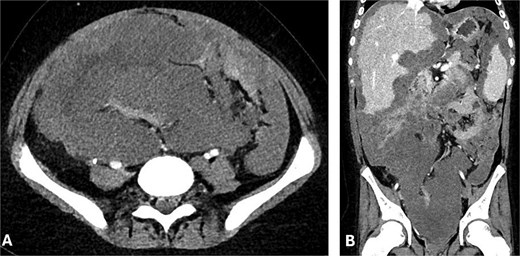

He received adjuvant FOLFOX and remained well on 3-monthly follow-ups. A positron emission tomography scan in September 2023 showed no recurrence. However, by April 2024, he presented with systemic symptoms and imaging revealed disease recurrence with extensive peritoneal involvement, ascites, pleural effusion, a 10 × 9.7 × 15.4 cm pelvic mass, and right mid-ureteric obstruction requiring stenting (Fig. 1).

(A) Axial and (B) coronal CT abdomen showing extensive conglomerate tumour masses with irregular margins and heterogeneous attenuation, encasing and displacing peritoneal structures.